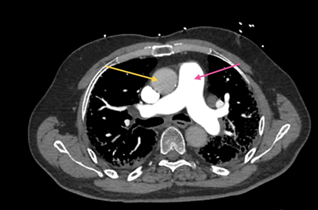

Figure 2: CT Chest with IV contrast, axial view, soft tissue

window, at the level of ventricles demonstrating enlarged right ventricle (pink

arrow) compared to left ventricle (yellow arrow), which is highly suggestive of

pulmonary arterial hypertension or right ventricular overload